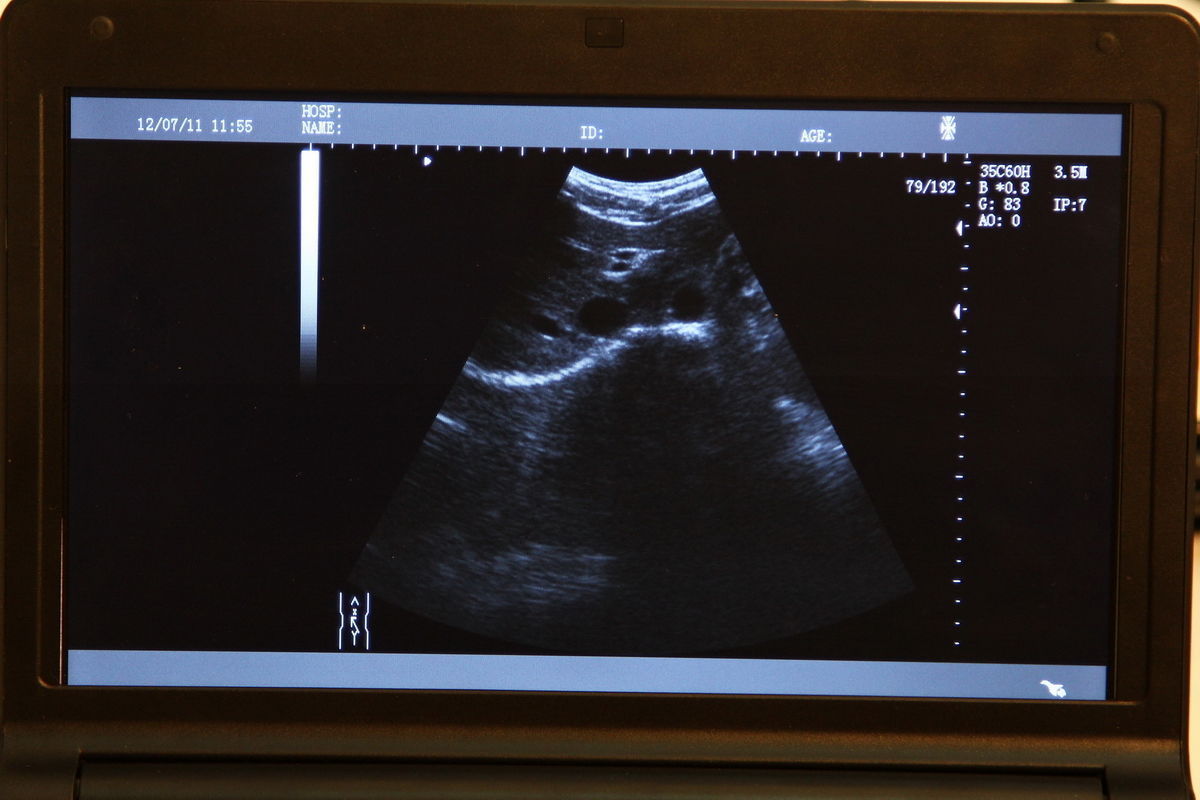

A 3D ultrasound scanner is a state-of-the-art imaging device used primarily in obstetrics. It creates detailed three-dimensional images of the fetus, providing healthcare professionals with critical information about the development and wellbeing of both the mother and baby. The 6.5 MHZ transvaginal probe enhances the accuracy of images, making it particularly useful in early pregnancy assessments. With this technology, doctors can visualize the fetus in real-time, leading to better diagnosis and treatment decisions.

Digital laptop 3D ultrasound scanners are portable and user-friendly, allowing healthcare providers to perform examinations in various settings, including clinics and hospitals. The digital format provides higher resolution images compared to traditional scanners, and since it uses advanced software, the analysis is faster and more reliable. This flexibility and efficiency revolutionize workflow, making it easier for medical professionals to access critical data quickly.